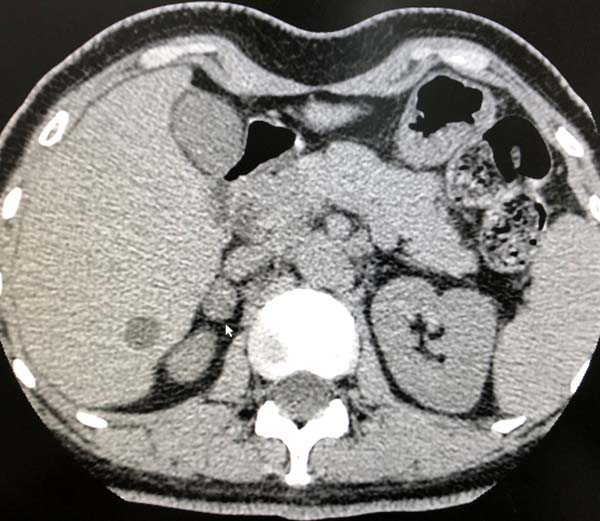

49岁的郭先生因“发现血压升高3个月,头晕1周”就诊于医院心内科门诊。高血压专科团队的主治医师高蕾接诊后考虑患者很可能是继发性高血压,就为患者调整了降压药物,将影响进行高血压激素检测结果的降压药物停用,换为无影响的特拉唑嗪。患者经过严格的药物洗脱2周后,收入心内科病房进行了规范的肾素醛固酮卧立位试验及卡托普利确证试验以及肾上腺的增强CT检查。结果发现患者双侧肾上腺结节,卧立位和确证试验结果都是阳性,原发性醛固酮增多症诊断成立,应进一步行双侧肾上腺静脉取血术(AVS),以确定优势侧,指导下一步手术治疗。

心内科的高血压专科团队立刻急性紧张的术前准备,制定围术期管理流程,梳理术中操作细节,准备手术耗材。8月11日上午,医院高血压专科团队在三楼导管室,成功施行了医院首例双侧肾上腺静脉采血术(AVS)。患者取平卧位在清醒状态下,经局麻穿刺右肘正中静脉,在X线透视指引下,选用特制导管成功在双侧肾上腺静脉、下腔静脉进行6部位取血送检。最终精准确定左侧肾上腺为分泌优势侧。术后患者经局部压迫止血后即可正常活动,与患者再次沟通,患者同意行左侧肾上腺切除手术。